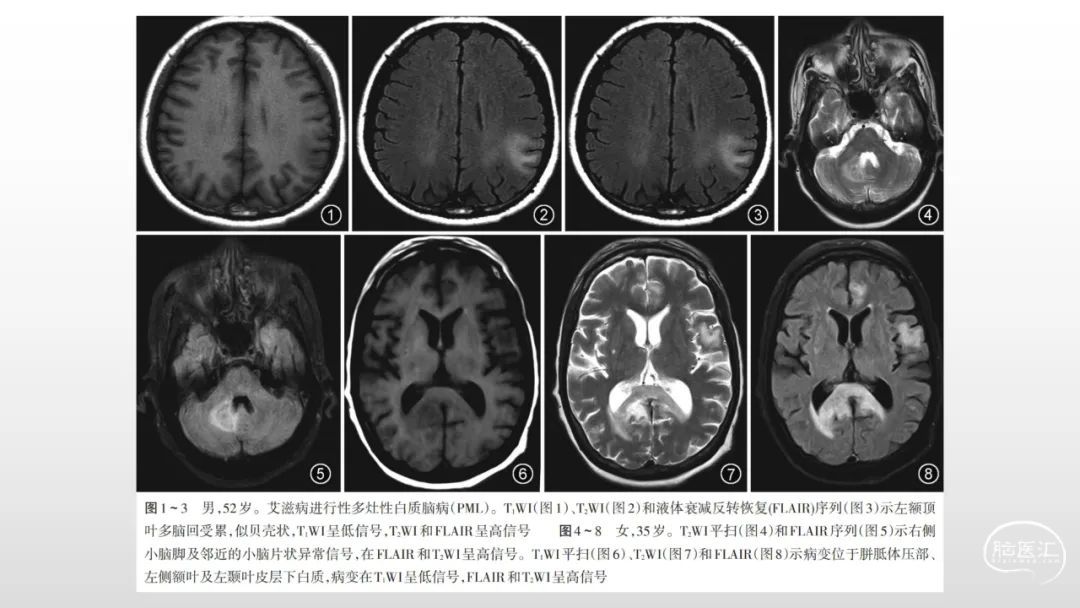

颅脑影像诊断基础知识讲座:感染和免疫性疾病2